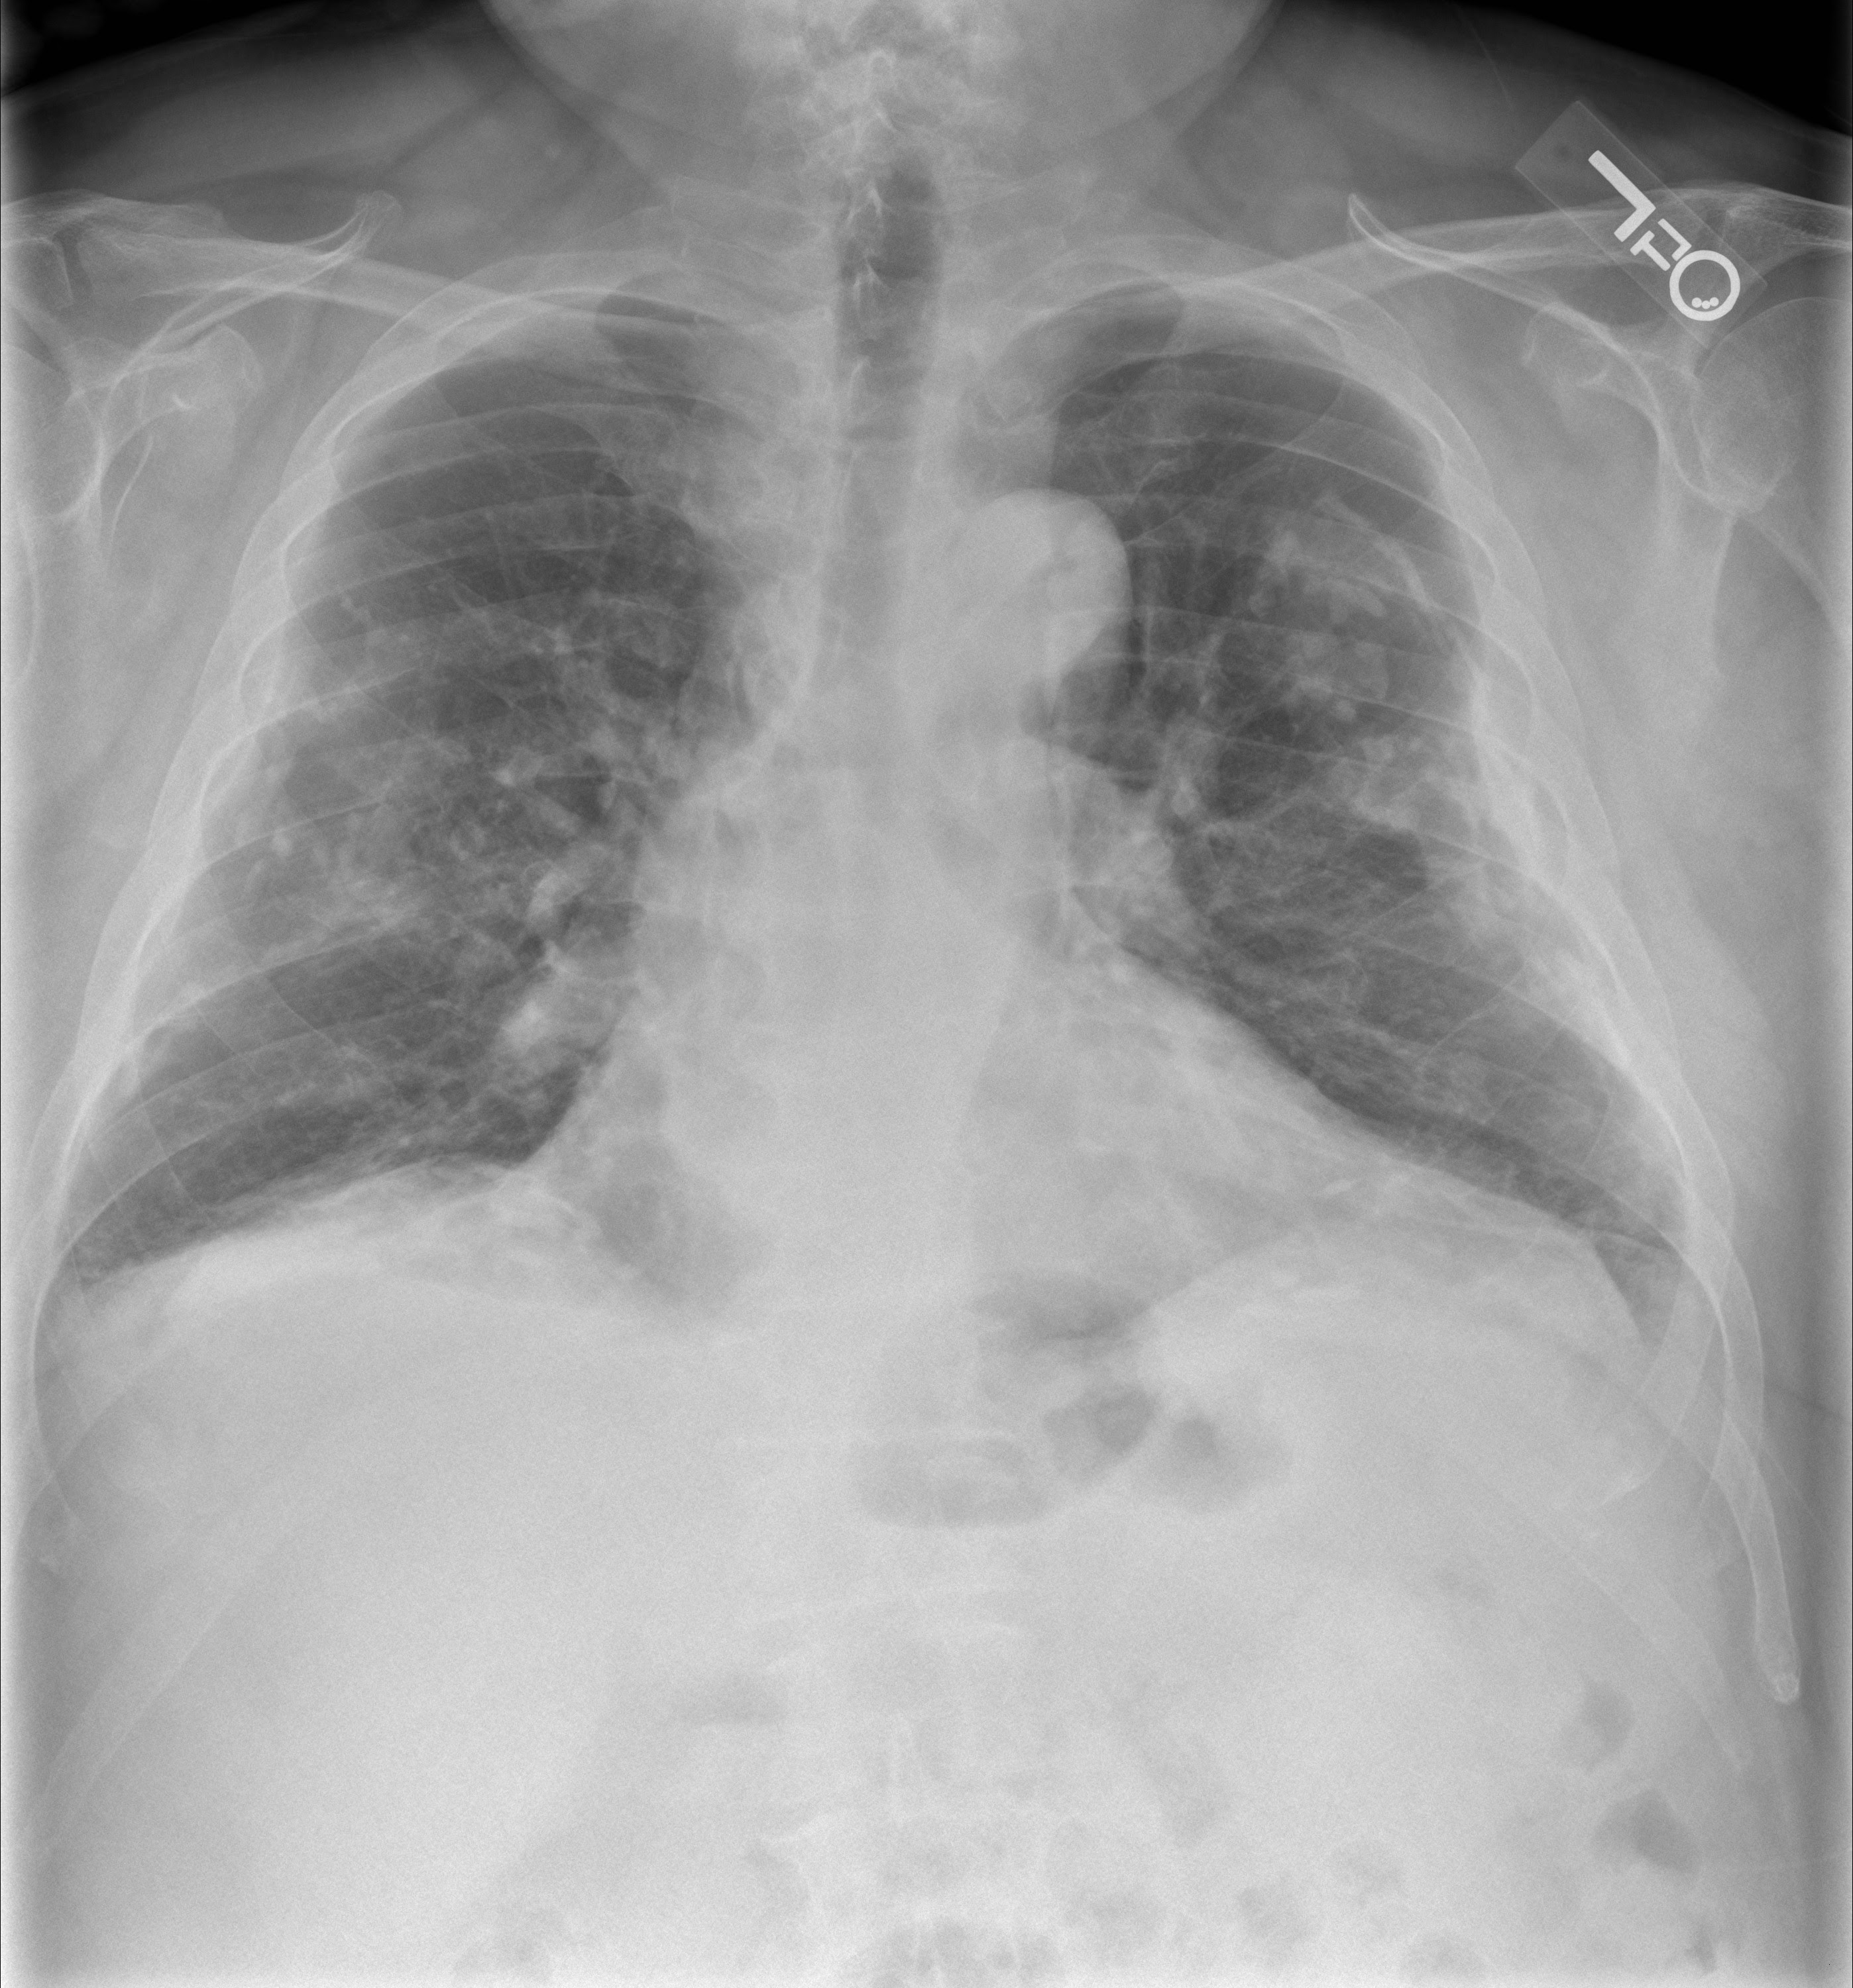

Q.136. A young patient presented with pleuritic chest pain, decreased breath sounds and chest movements on the right side. No history of trauma, X-ray was given. What is the next appropriate step?

Correct Answer : C

The patient presents with pleuritic chest pain, decreased breath sounds, and reduced chest movements, raising concern for a lung collapse or mass. A CT scan provides detailed images to identify issues like pneumothorax, pleural effusuion, lung mass. It also helps in determining the severity of the issue and guides treatment.